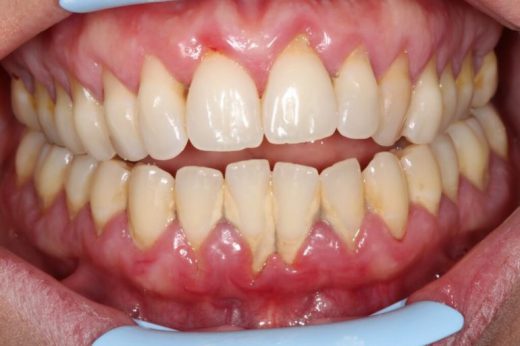

La Parodontologia è un ramo dell’Odontoiatria, che si occupa dello studio delle malattie che riguardano la bocca ed in modo particolare dei denti. Il parodonto è costituito da : gengiva; osso alveolare; cemento radicolare...